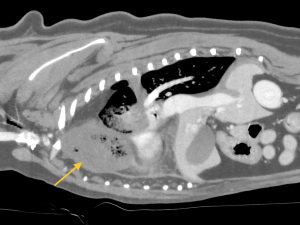

こんにちは。獣医師の永井です。 今回は肺葉捻転についてです。 犬猫の肺はバナナの房のように前葉、中葉、後葉(副…]]>

こんにちは。獣医師の永井です。 今回は肺葉捻転についてです。 犬猫の肺はバナナの房のように前葉、中葉、後葉(副…]]>